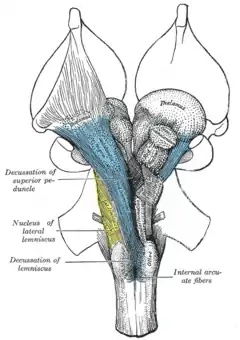

A decussation (from Latin decussis 'ten', written as a capital X) refers to nerve fibers that cross the sagittal plane from one side of the central nervous system to the other, and connect different brain regions. There are two kinds:

- Type 1 crosses the sagittal plane in the same brain region or spinal segment where the cell body is located. Examples are Mauthner cells in fish and amphibians.

- Type 2 crosses the sagittal plane in a different brain region. Example: pyramidal decussations.

The first type is known also for invertebrates, whereas the second type only occurs in vertebrates. The second type is thought to be due to an axial twist, such that each hemisphere of the forebrain represents predominantly the contralateral side of the body.

The brainstem from the front, showing a decussation of the superior pedicle and lemniscus, where nerve fibres from one side cross over to the next

The brainstem from the front, showing a decussation of the superior pedicle and lemniscus, where nerve fibres from one side cross over to the next The optic chiasm in the human brain, showing pathways conveying information from the visual field of each eye to the contralateral visual cortex